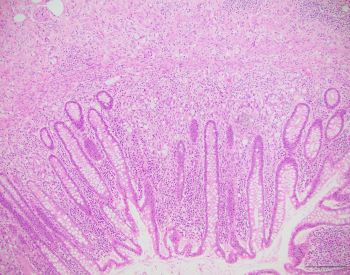

A 43-year-old female presents with chronic unexplained diarrhea. Colonoscopy shows...

Case History